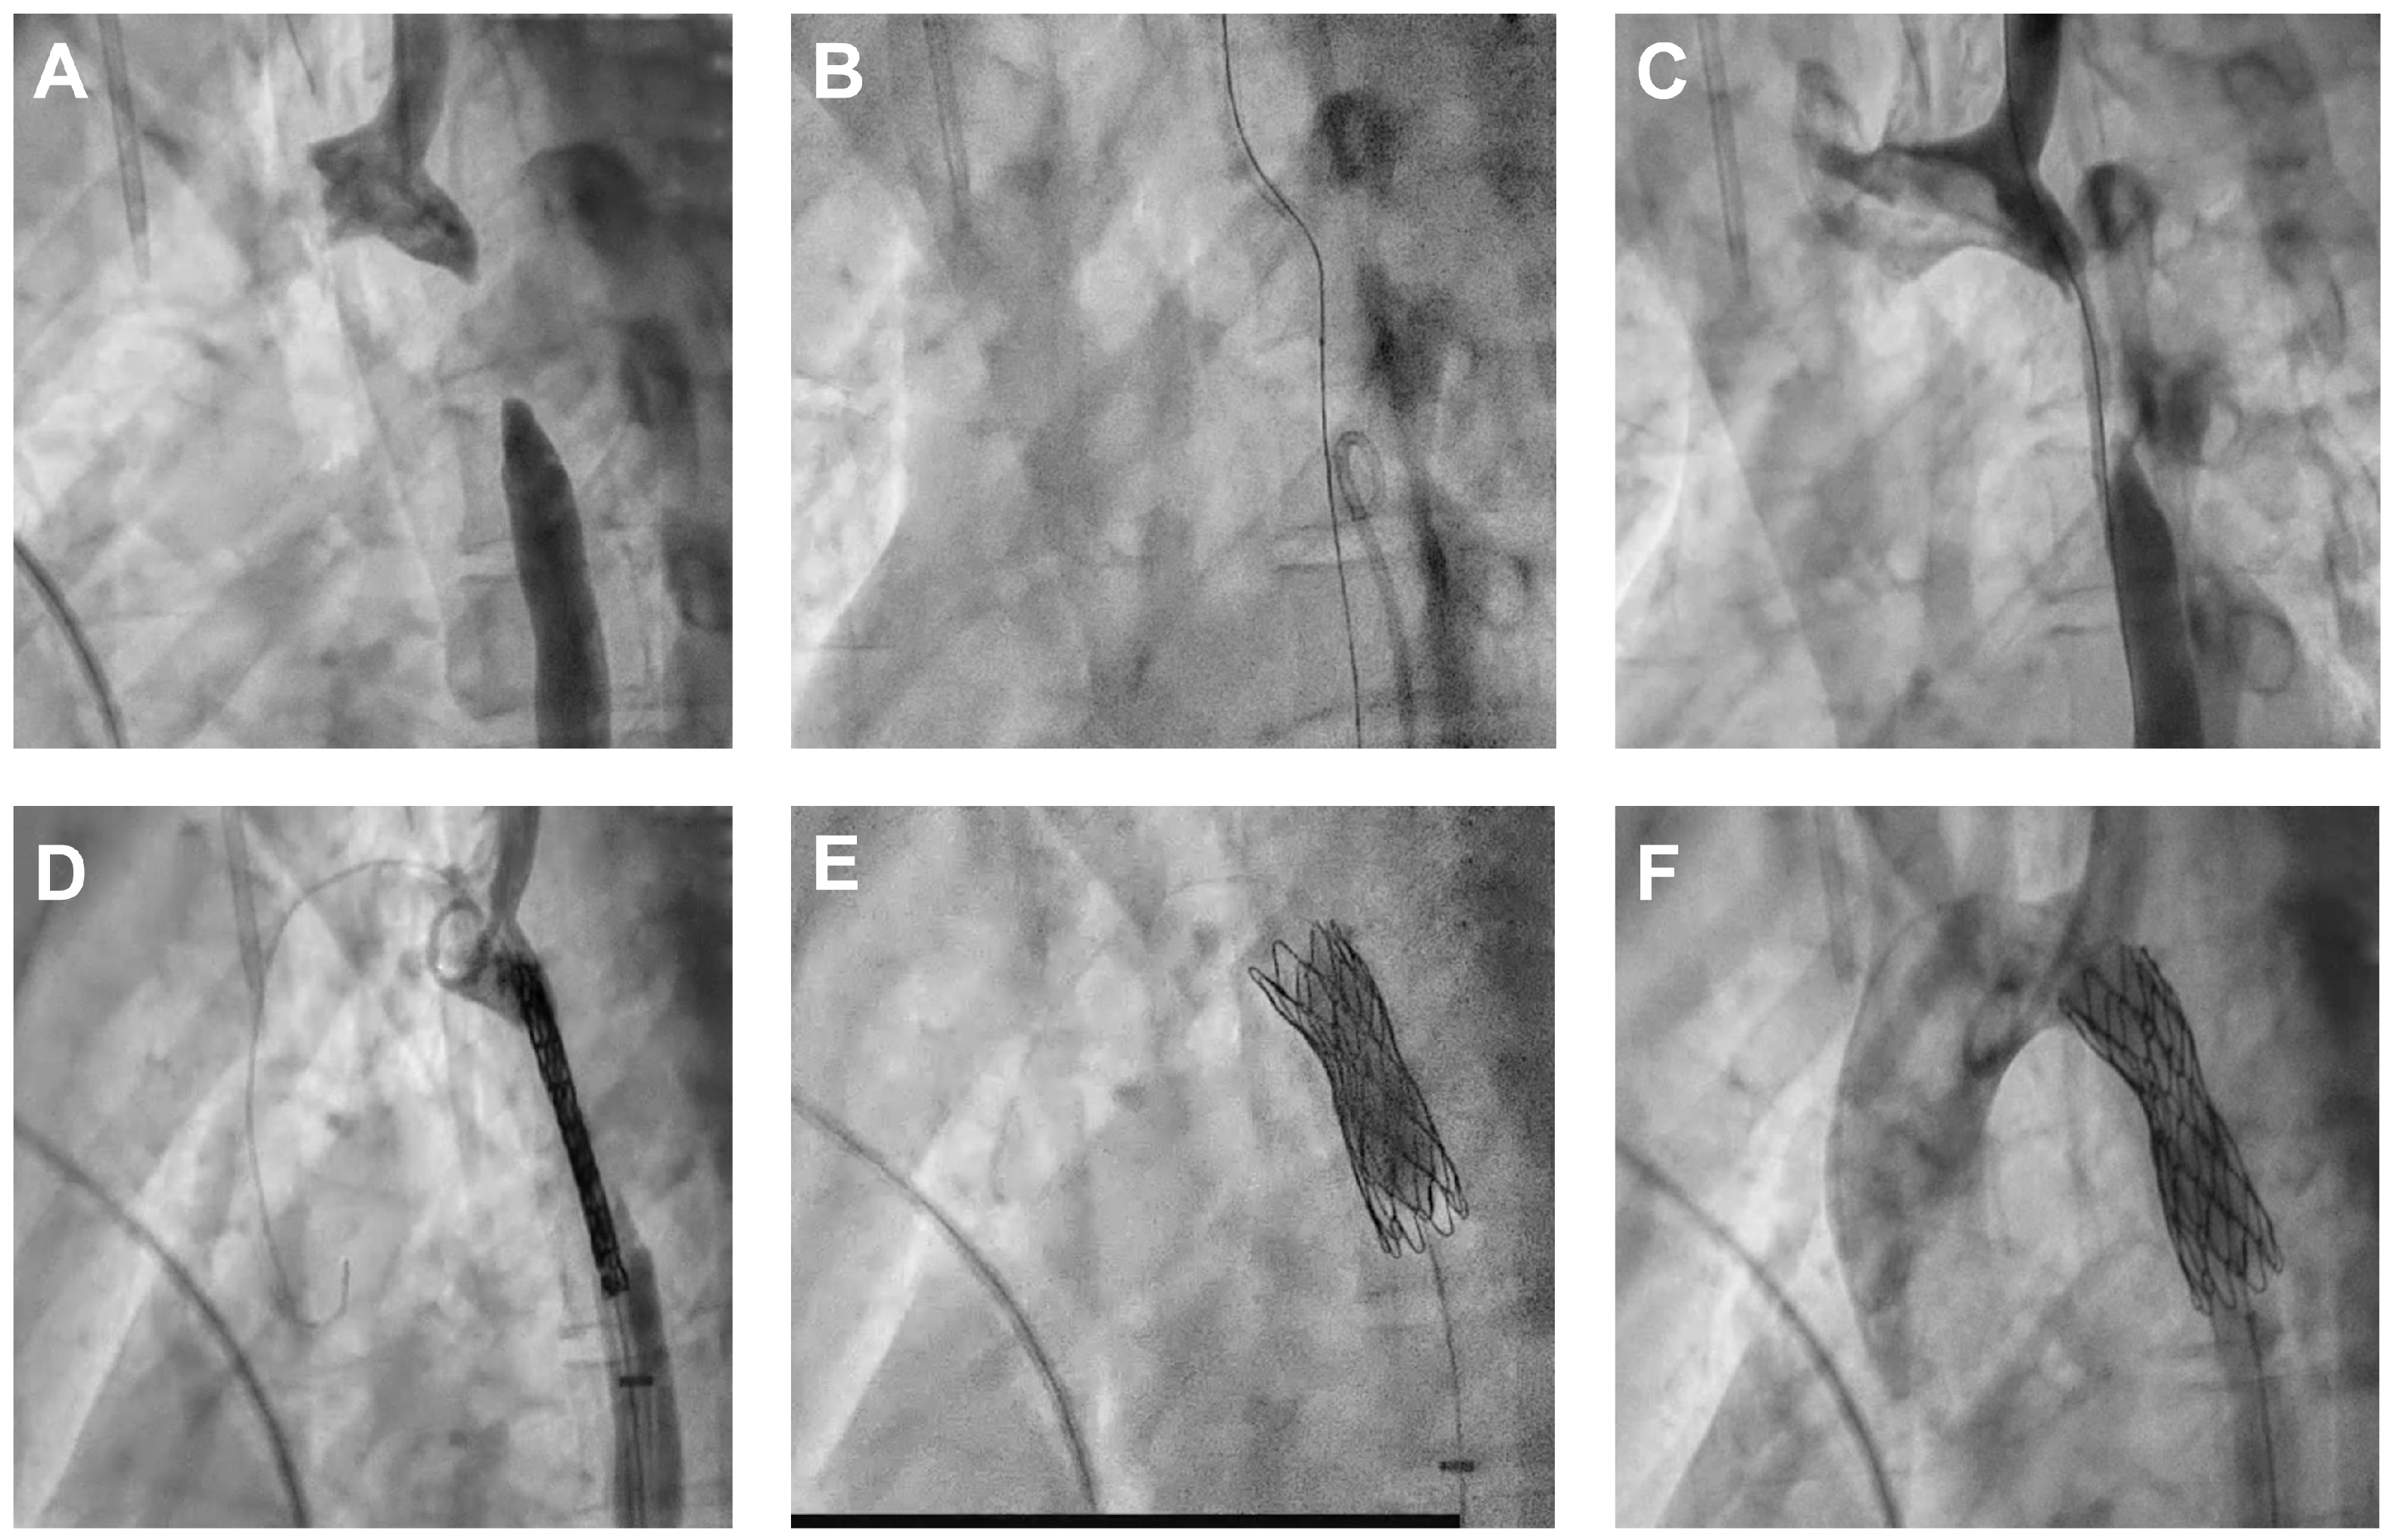

Simultaneous contrast injection via an MPA2 6F catheter at the proximal descending thoracic aorta and a retrograde injection via a Pigtail 6F catheter at the diaphragmatic level reveal a narrowing of the aortic lumen, followed by total occlusion.

Contrast injection from the right femoral artery pigtail catheter confirms the positioning in the true aortic lumen.

A Pigtail 6F catheter used for antegrade contrast injection via the proximal access (radial/brachial) confirms the correct placement of the proximal end of the introducer sheath.

Finally, a 45 mm Cheatham Platinum covered stent (NuMed Inc., New York, NY, USA) is mounted on a BIB 12/45 mm balloon (NuMed Inc., New York, NY, USA) and deployed at the coarctation site.

Following stent deployment, blood pressure measurements proximal and distal to the stent are ideally equal, with no residual pressure gradient. Angiographic assessment of the aortic arch demonstrated a well-expanded and well-positioned stent must be with no signs of proximal or distal dissection (Figure 4).